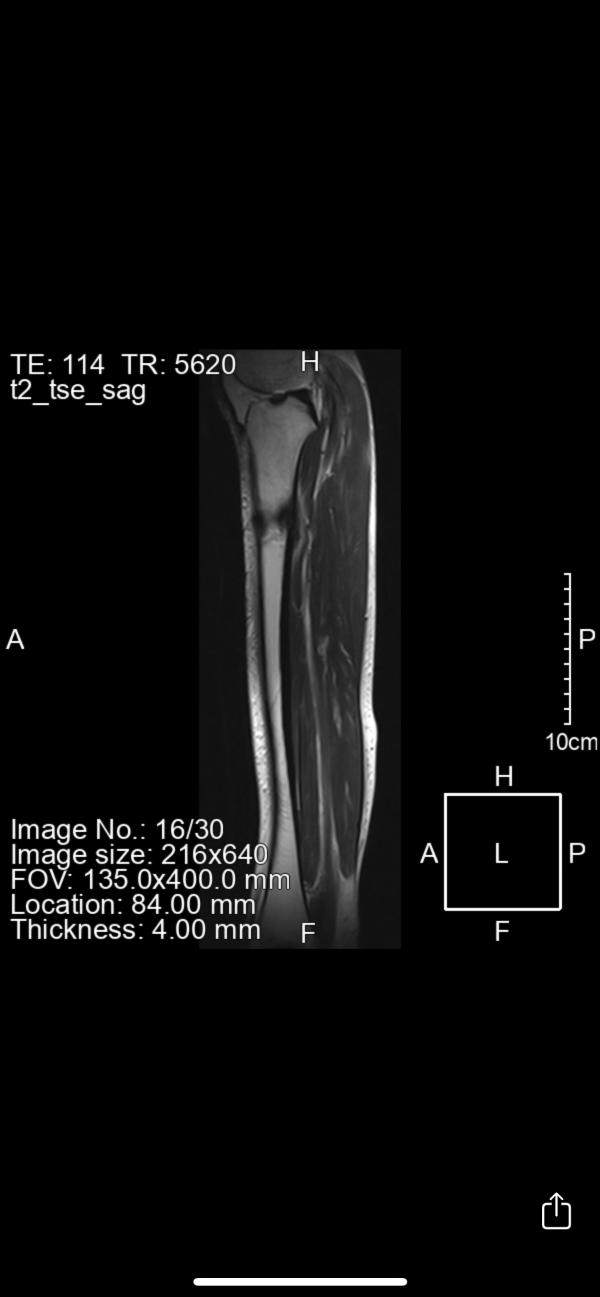

1 октября была спортивная травма , поставили стресс-перелом,лечила . Далее делала МРТ,КТ после которых направили к онкологу . 2 врача сказали что мол все нормально,вы зря паникуете и без назначения анализов опровергающих описание МРТ отправили домой. Я ,в надежде что все хорошо,продолжаю лечение стресс-перелома и сегодня делаю контрольное МРТ , на котором видны не улучшения ,а ухудшения😭

1 фото это МРТ в начале,2 которое сделала вчера. За 2 месяца это все расползлось и снова отправляют к онкологу😔

Костная ткань так же изменена и + изменен картикальный слой (раньше этого не было)